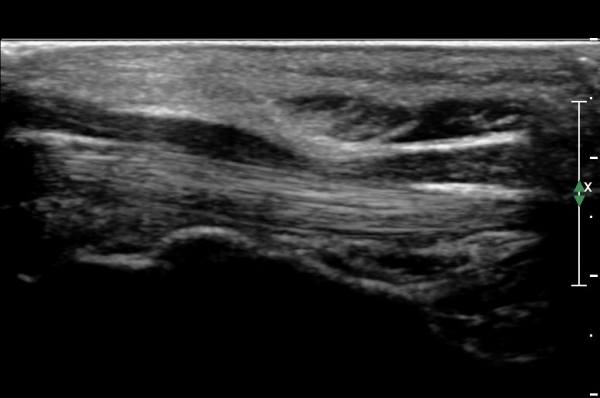

¼ö±Ù°ü ¸»´ÜºÎÀ§(trapezium, capitate level)¿¡¼­ Á¤Á߽Űæ Ⱦ´Ü¸é°Ë»ç»ó Á¤Á߽ŰßÀÇ ÆíÆòÈ­°¡ °üÂûµÊ(»çÁø 3).